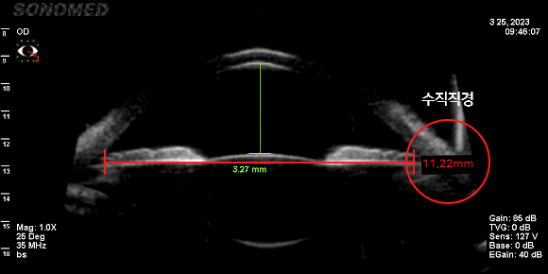

평균적으로 수직 직경이 수평 직경보다 길기 때문에 수직형 V-토릭 ICL은 넓은 공간에 여유 있는 사이즈의 렌즈가 삽입되어

렌즈 주변부의 접촉이 없어 렌즈삽입술의 부작용을 방어하고 안정성이 높습니다.-

수평 안구 공간 측정 (11.22mm)

수직 직경 공간이 더 넓음